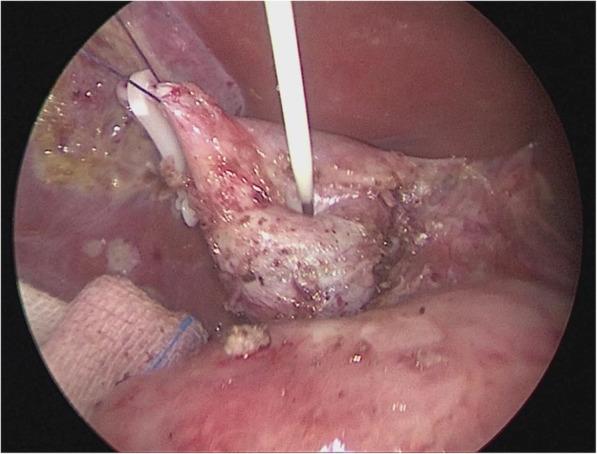

A modified technique of single-incision laparoscopic hepaticojejunostomy for children with choledochal cysts.

To present a modified laparoscopic surgical technique that works to optimize the surgical view in laparoscopic total excision of choledochal cyst in pediatric patients.

METHODS

From June 2015 to June 2017, a total of 48 pediatric cases of choledochal cyst were admitted. Their age ranged from 15 month to 8 years (average 3.5 years). The Todani types were: type I (n = 32) and type IVa (n = 16), according to the diagnostic criteria of ultrasound, abdominal computed tomography (CT) and magnetic resonance cholangiopancreatography (MRCP).

RESULTS

Total cystic excision with hepaticoenterostomy was accomplished laparoscopically in 48 cases with our transumbilical single -incision method without conversion to open surgery. Average duration of operation was 200 min (range 170-240 min), average intraoperative blood loss was 9 ml (range 6-14 ml) without the need for blood transfusion. The 72-h postoperative ultrasound reported no abdominal effusion, when the intraperitoneal drainage tube was removed. There was no postoperative complication during the 6 months of follow-up.

CONCLUSIONS

We accomplished the same postoperative outcome in laparoscopic total cyst excision with our modified method as that with conventional laparoscopic surgery. This technique allows the operator to have a stabilized surgical view without needing to rely on an assistant to hold up the liver lobe for larger operative space.